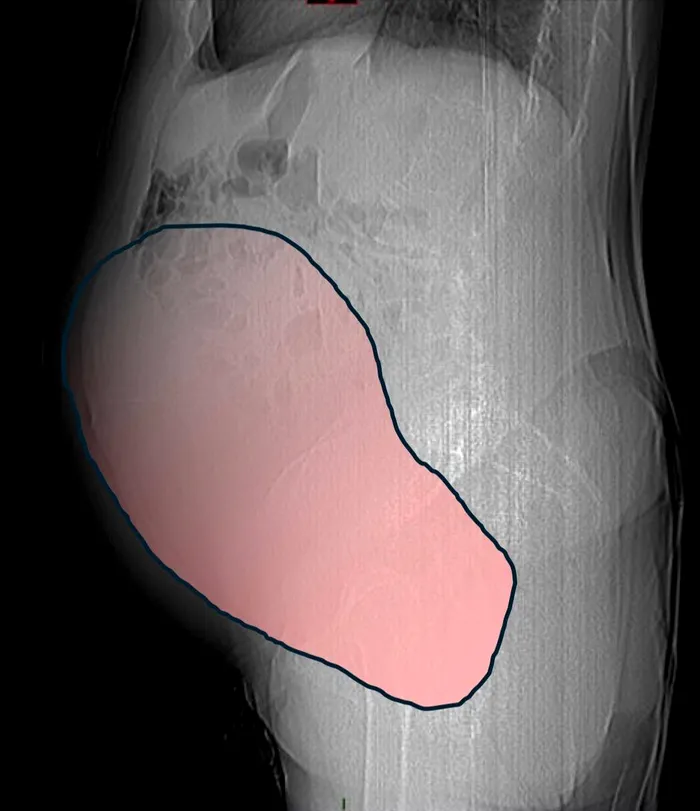

Timp de luni de zile, chistul ovarian gigant, cu un diametru de aproximativ 28 de centimetri, a rămas ascuns, fără a da semne evidente. Pacienta nu observase nimic.

În timpul operației, gravitatea situației a devenit evidentă. Tumora ovariană gigantică a fost îndepărtată: cântărea aproximativ 6 kilograme, având un volum comparabil cu cel al unei sarcini gemelare la termen. Cele mai periculoase simptome erau legate de tulburările intestinale, care necesitau intervenția imediată și coordonată a mai multor specialiști.